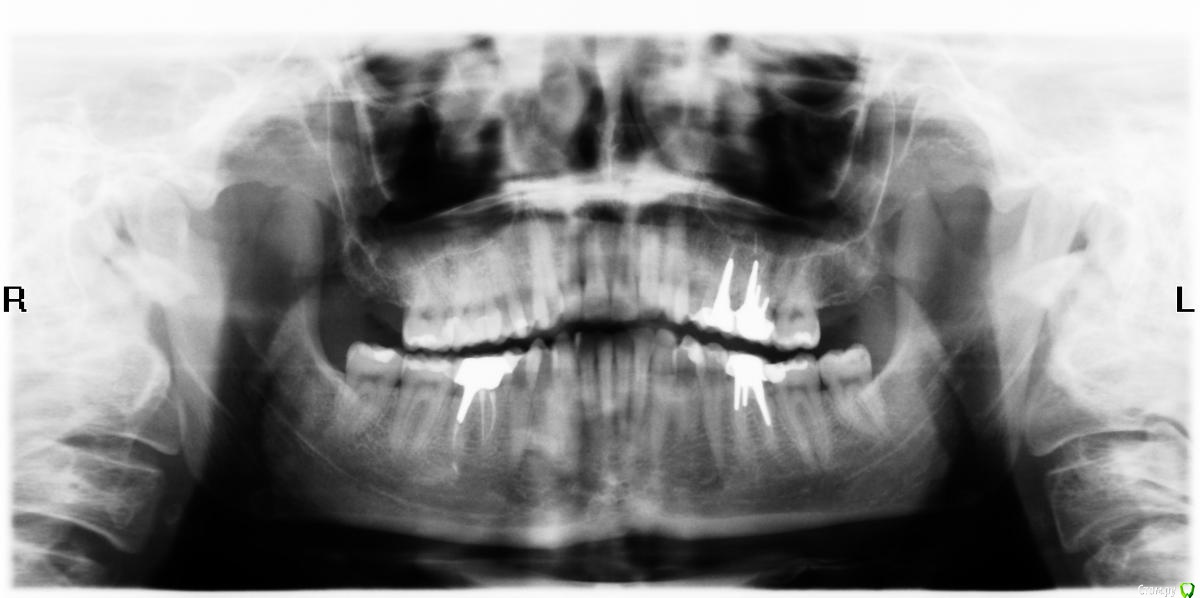

TAP Опубликовано 11 января, 2015 Поделиться Опубликовано 11 января, 2015 Добрый день! Прокомментируйте, пожалуйста, ортопантомограмму! Ссылка на комментарий

diesel87 Опубликовано 12 января, 2015 Поделиться Опубликовано 12 января, 2015 Нет двух верхних восьмерок 2 Ссылка на комментарий

red_butler Опубликовано 12 января, 2015 Поделиться Опубликовано 12 января, 2015 снимок плохого качества Ссылка на комментарий

SDC Опубликовано 13 января, 2015 Поделиться Опубликовано 13 января, 2015 Да пока нет конкретных вариантовСначала нужно определиться с Доком, затем к нему на осмотр и очную консультацию.Ортопантомограмма не самый лучший вид рентгендиагностики, а Ваша не самая качественная из них.Явных и заметных проблем на снимке нет, но Ваш подход к состоянию здоровья требует иной диагностики. 1 Ссылка на комментарий

TAP Опубликовано 13 января, 2015 Автор Поделиться Опубликовано 13 января, 2015 Пока едиственное дополнительное пожелание, помимо общего состояния здоровья, это найти врача, которому можно доверить извлечение серебряно-палладиевой вкладки из двухканального зуба в москве. Ссылка на комментарий

SDC Опубликовано 13 января, 2015 Поделиться Опубликовано 13 января, 2015 Да, если дальше еще не так заметно, то хотя бы на 25м.у вкладки, которой восстановлен 25 зуб, довольно мощный и длинный штифт, будьте заочно готовы к замене зуба на имплантат - в случае разбора 25 весьма вероятен такой финал. Ссылка на комментарий